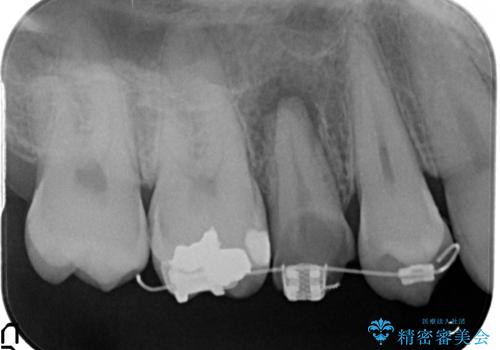

歯の健康な部分を矯正治療で引っ張り出してから、虫歯治療を行なっています。

治療途中

保険治療の範囲ですと予後が期待できません。自費治療では、エクストリュージョンなど選択肢が広がり、しっかりその歯を悪くならない状態に持っていくことが可能です。